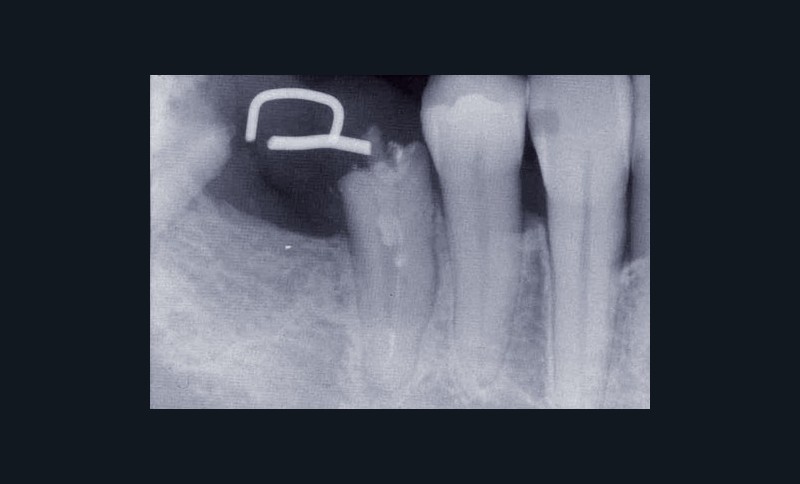

Les examens cliniques et radiographiques montrent une parodontite chronique généralisée (fig. 1a à m).

Nous décidons d’entreprendre une thérapeutique initiale parodontale classique dans tous les secteurs, y compris l’extraction de 24, un bridge de 45 à 48 avec 46 en pontique, un bridge complet de contention de 17 à 27 sur 11 piliers dentaires et une greffe épithélio-conjonctive sur 31. Cette dernière ne sera jamais réalisée. Le bridge maxillaire permettra de réduire le surplomb antérieur et d’améliorer le sourire de la patiente, ce qui constitue l’une de ses demandes.